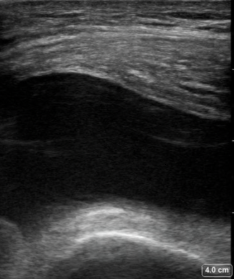

Foot Doesn’t Work Right

A 35-year-old male felt a painful “pop” in his posterior left lower leg while playing football. Afterwards his “foot didn’t work right anymore.” X-ray of the left ankle and tib/fib are normal but he is unable to ambulate. You place an ultrasound over the area of maximal tenderness and discover the following: